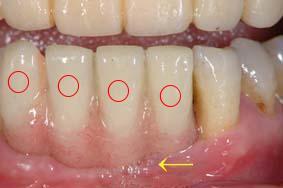

その3 は、プロビジョナル・レストレーションで使用する即時重合レジン(私の場合、 GC のライブピンクです)と残存歯肉の色調がどれだけ近いか、またはどこがどのように違うのかを判断して、歯肉部のシェードテイキング

とする場合です。

歯肉色・プロビレジンとの比較

の部分がインプラントのプロビジョナル・レストレーションですが、歯肉部の色調はセラミックにする際に参考にします。  は境目ですが、それ程大きな差はないので参考にし、色調再現をする訳です。手元に歯肉部のレジンもありますから、ステップごとに比較しながら製作すれば、大体合わせることは難しいことではりません。